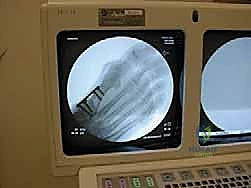

2. التصوير الإشعاعي المتقدم (X-Rays):

التصوير بالأشعة السينية أثناء الوقوف (Weight-bearing X-rays) هو المعيار الذهبي للتشخيص. يطلب الدكتور هطيف صوراً من زوايا محددة (أمامية خلفية، جانبية، ومنظور العظام السمسمانية).

من خلال هذه الأشعة، يقوم الدكتور هطيف بقياس زوايا حاسمة تحدد خطة العلاج، أهمها:

* زاوية إبهام القدم الأروح (HVA - Hallux Valgus Angle): الزاوية بين المشط الأول والسلامية الدانية. (الطبيعي أقل من 15 درجة).

* الزاوية بين المشطين (IMA - Intermetatarsal Angle): الزاوية بين المشط الأول والمشط الثاني. (الطبيعي أقل من 9 درجات).

* تقييم مفصل العظام السمسمانية (Sesamoid Station): لمعرفة مدى انزلاق المشط عن هذه العظام.

بناءً على هذه القياسات الدقيقة، يصنف الدكتور هطيف الحالة إلى خفيفة، متوسطة، أو شديدة، ويقرر التدخل الأنسب. في الحالات الشديدة (IMA > 15 درجة)، تكون عملية قطع عظم شيفرون الداني بالصفيحة المغلقة هي الخيار الأمثل.